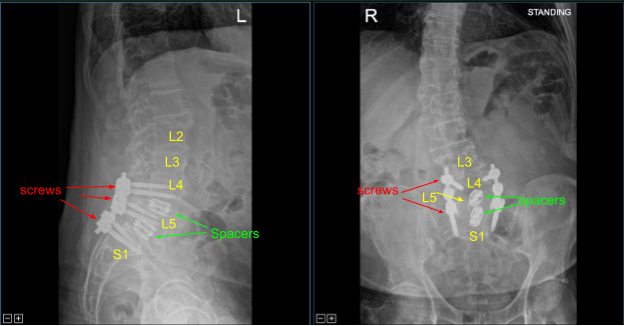

Expandable titanium interbody spacers, 15-degree lordotic at L5-S1 and 10-degree lordotic at L4-5, were placed under fluoroscopic guidance and expanded to proper fit. There was partial subsidence of the interbody spacer at L5-S1 into the L5 body, but it was secured and tight fit and imaging showed midline positioning.

CT scan was then obtained (shown above) which showed correct positioning of all the hardware. Neuromonitoring signals were stable. The wound was irrigated copiously. Bilateral transverse processes were decorticated for posterolateral arthrodesis from L4 to S1.

Precut titanium rods were contoured with rod benders and placed across the screw tulips from L4 to S1and secured with locking caps which were all final tightened with a torque and anti torque device. Final AP and lateral x-rays showed correct and complete hardware implantation.